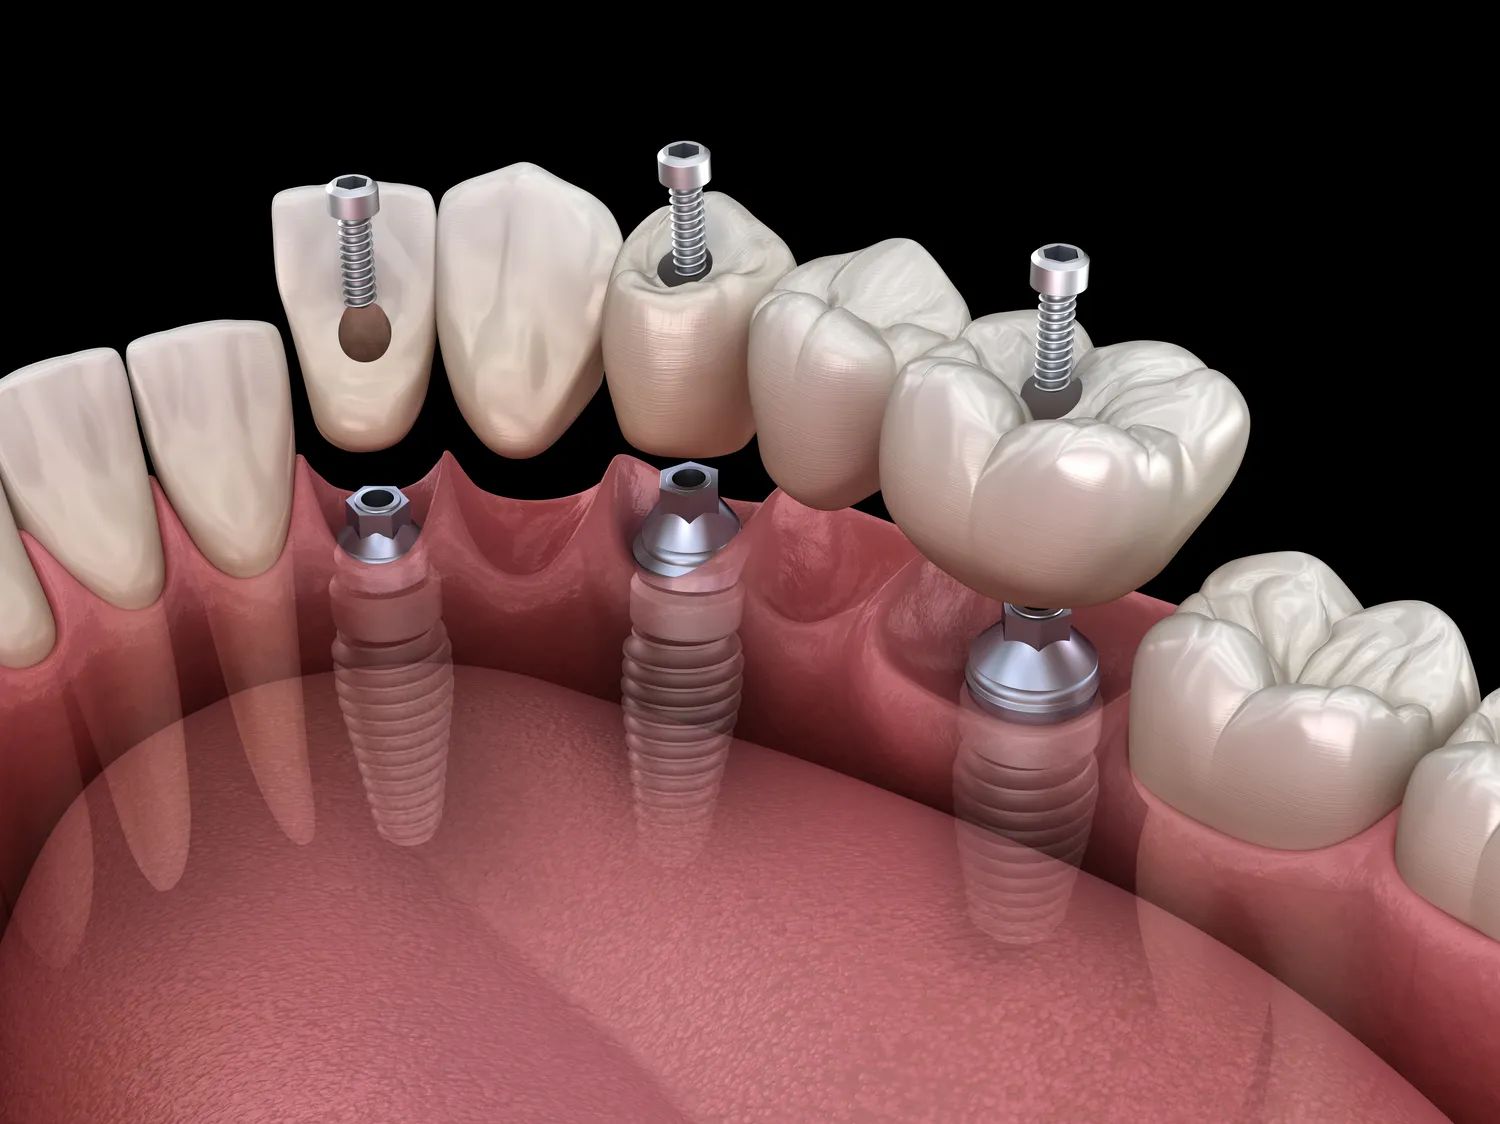

Proces zakupu implantów zębowych w Lublinie zazwyczaj rozpoczyna się od konsultacji ze stomatologiem, który oceni stan zdrowia jamy ustnej pacjenta oraz zaproponuje odpowiedni plan leczenia. Podczas pierwszej wizyty lekarz przeprowadzi szczegółowy wywiad medyczny oraz wykona zdjęcia rentgenowskie lub tomografię komputerową, aby dokładnie ocenić warunki anatomiczne do wszczepienia implantu. Następnie pacjent otrzymuje informacje dotyczące kosztów oraz czasu trwania leczenia. Po zaakceptowaniu planu leczenia następuje etap chirurgiczny, podczas którego implant jest wszczepiany w kość szczęki lub żuchwy. Po kilku miesiącach następuje etap odbudowy protetycznej, kiedy to na implancie mocowane są korony zębowe. Cały proces może potrwać od kilku miesięcy do nawet roku, w zależności od indywidualnych potrzeb pacjenta oraz ewentualnych dodatkowych zabiegów wymaganych przed wszczepieniem implantu.

Czas gojenia po wszczepieniu implantów zębowych może się różnić w zależności od indywidualnych uwarunkowań pacjenta oraz specyfiki danego przypadku klinicznego. Zazwyczaj proces ten trwa od kilku tygodni do kilku miesięcy. W pierwszym etapie następuje integracja implantu z kością szczęki lub żuchwy – to kluczowy moment dla sukcesu całego leczenia. W tym czasie ważne jest przestrzeganie zaleceń lekarza dotyczących diety oraz higieny jamy ustnej, aby zapewnić optymalne warunki do gojenia się tkanek. Po około trzech do sześciu miesięcy lekarz oceni stan implantu i zdecyduje o dalszych krokach – jeśli wszystko przebiega prawidłowo, można przystąpić do etapu odbudowy protetycznej polegającej na mocowaniu koron na wcześniej wszczepionych implantach. Warto pamiętać, że każdy organizm reaguje inaczej i czas gojenia może być wydłużony u osób z problemami zdrowotnymi czy osłabionym układem odpornościowym.